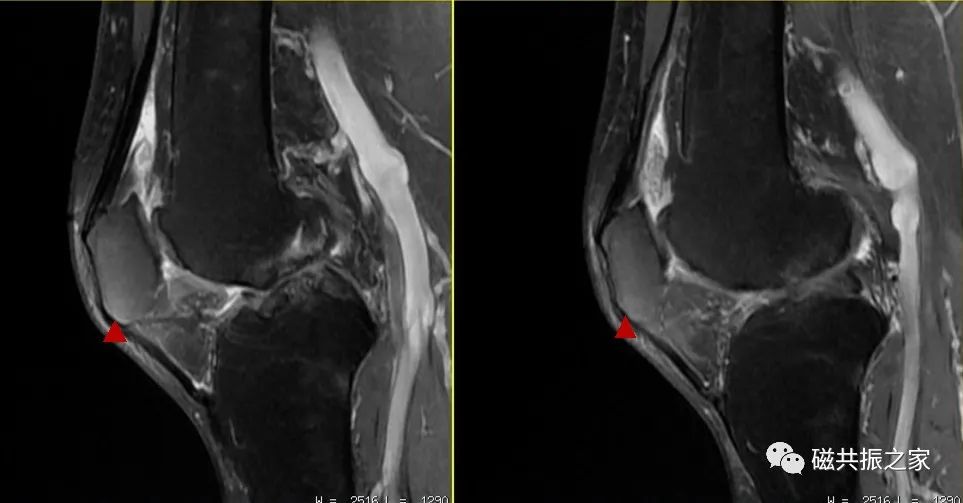

如上图△,图像中三角区域类型水肿信号的表现,其很容易被误诊;重新摆位后下图▽。

图像中局部区域的“水肿”信号消失。实践告诉我们,在四肢关节的扫描中,绝大多数的伪影都是由于摆位不合理造成的。

图△,这类伪影在四肢关节的扫描中并不少见。如不能正确地识别该类伪影,其很容易被误诊为水肿信号。在四肢关节的扫描中正确认识相应的伪影 ,是获得优异图像质量的关键。同时对相应伪影的正确认识,可以有效避免漏误诊的发生。